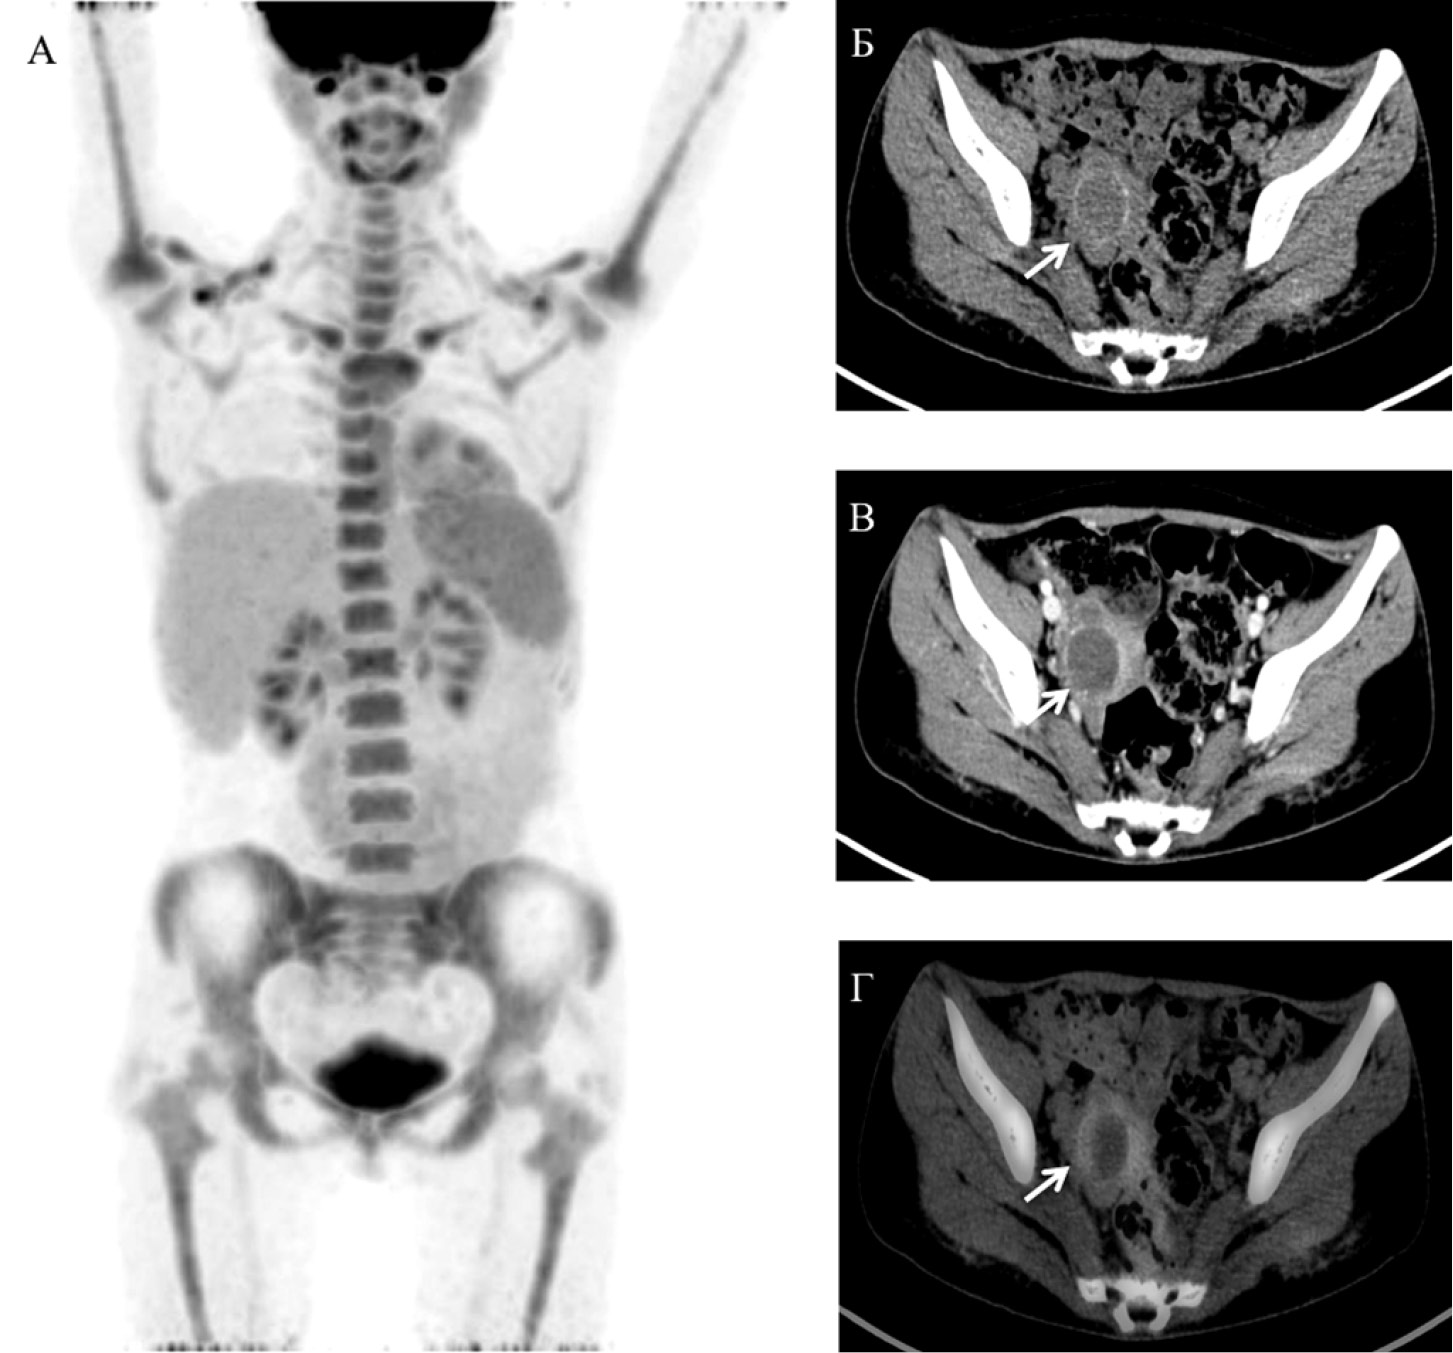

Для уточнения локализации резистентной опухоли больной выполнена ПЭТ/КТ с 18F-ФДГ. В результате установлено: в области дна матки справа отмечается невысокая фиксация 18F-ФДГ (макс SUV 2,73) по периферии крупного узлового образования размерами до 3,2 см (рис. 4).

Рис. 4. Позитронная эмиссионная томография (MIP-реконструкция) во фронтальной проекции (А), компьютерная томография без контрастного усиления (Б), КТ с внутривенным контрастным усилением (В), совмещённое ПЭТ/КТ-изображение (Г) в аксиальной проекции. Стрелками указано неинтенсивное повышение накопления 18F-ФДГ (Г) по периферии узлового образования в области дна матки справа (Б, В)

Больной выполнена органосохраняющая гистеротомия, иссечение резистентного узла матки в пределах здоровых тканей, тубэктомия справа (рис. 5).

Гистологическое заключение: Фрагменты миометрия с полостью, выполненной некротическими массами, кальцинатами, гемосидерофагами, без признаков резидуальной опухоли.

В послеоперационном периоде отмечалась нормализация уровня β-ХГЧ. Дополнительное лечение не проводилось.